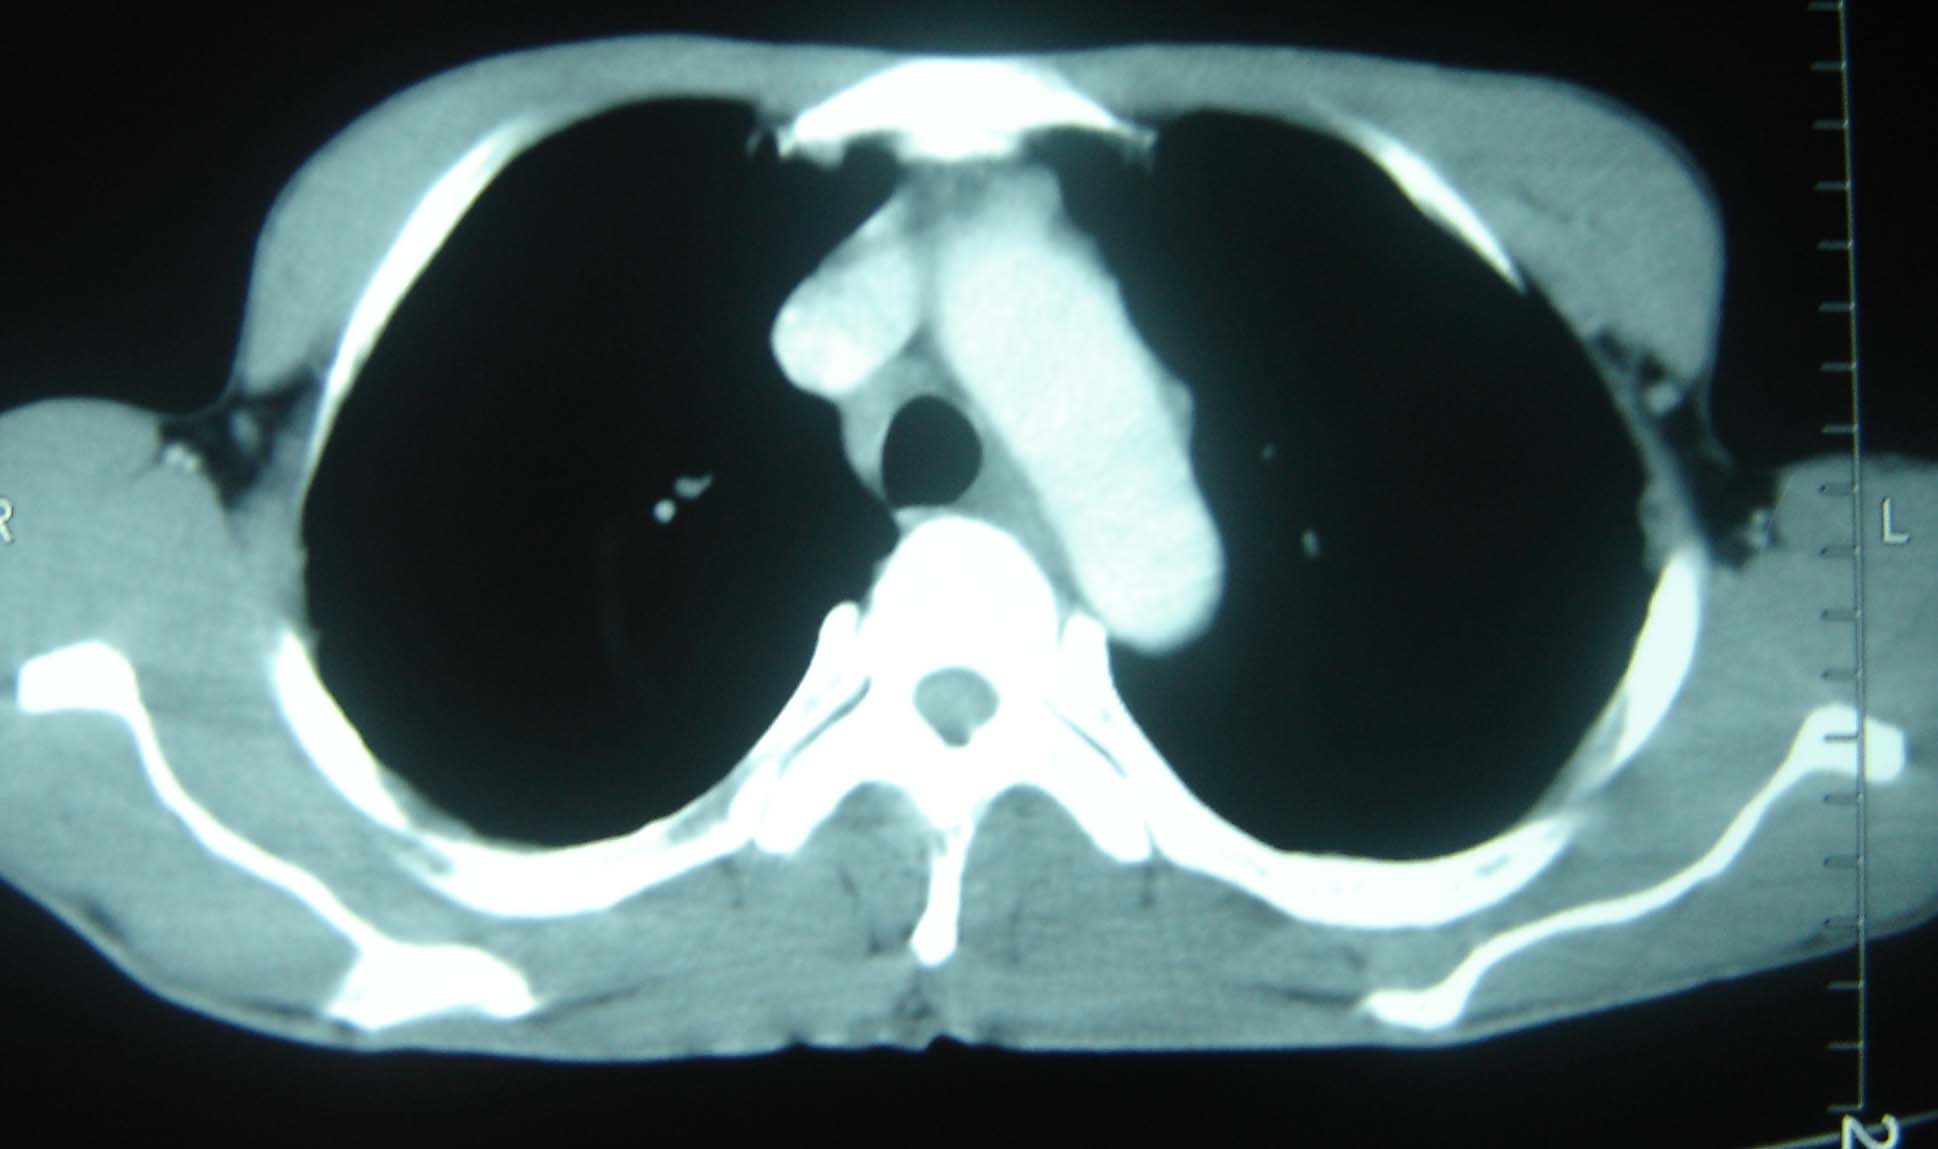

男 、43岁,咳嗽胸痛,装修工,平时接触粉尘较多,有吸烟史10多年,纤维支气管镜检查未发现异常,胃镜、腹部b超检查亦未发现异常,颈部淋巴结活检未发现肿瘤细胞。

不能排除转移,如果不能找到原发灶,只有短期随访。

结节病?转移瘤?

结节病。

转移瘤?

转移

1)考虑双肺及胸膜多发性转移瘤。2)肺气肿。

双肺结节病。